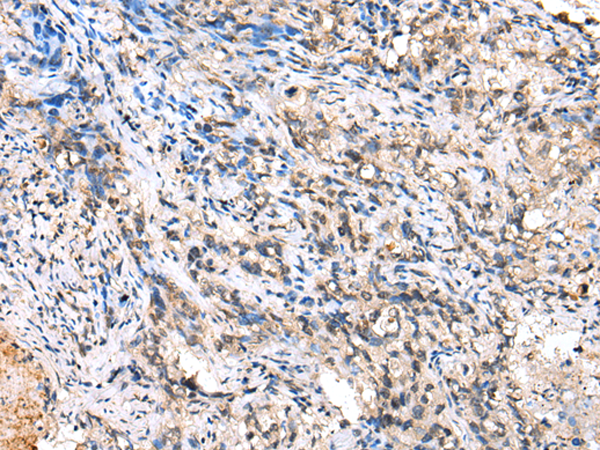

分类: 科研抗体货号: P00094别名: MGC104475应用: IHC反应种属: Human, Mouse